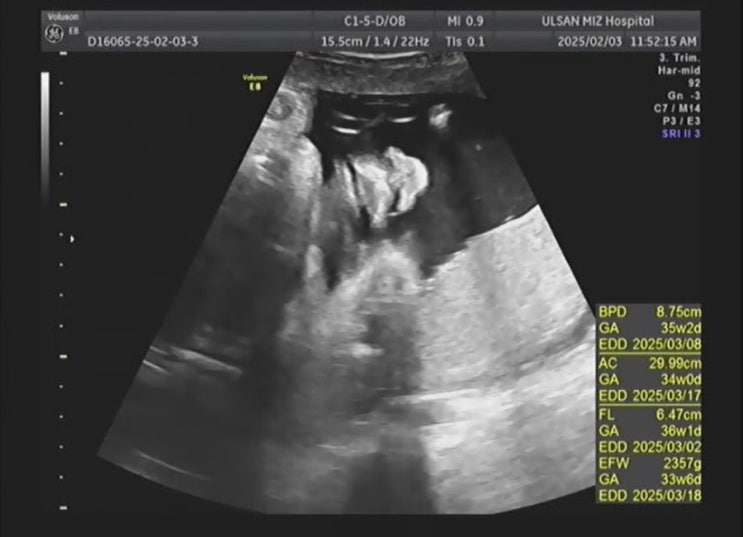

[임신36주] 작은아기, 배뭉침 잦음, 병원에 가야되는 배뭉침(자궁수축) 기준?

35주에 막달검사를 하고 매주 병원 진료를 간다. 태동검사 20분정도 하기때문에 시간 여유를 두고 가는게 ...